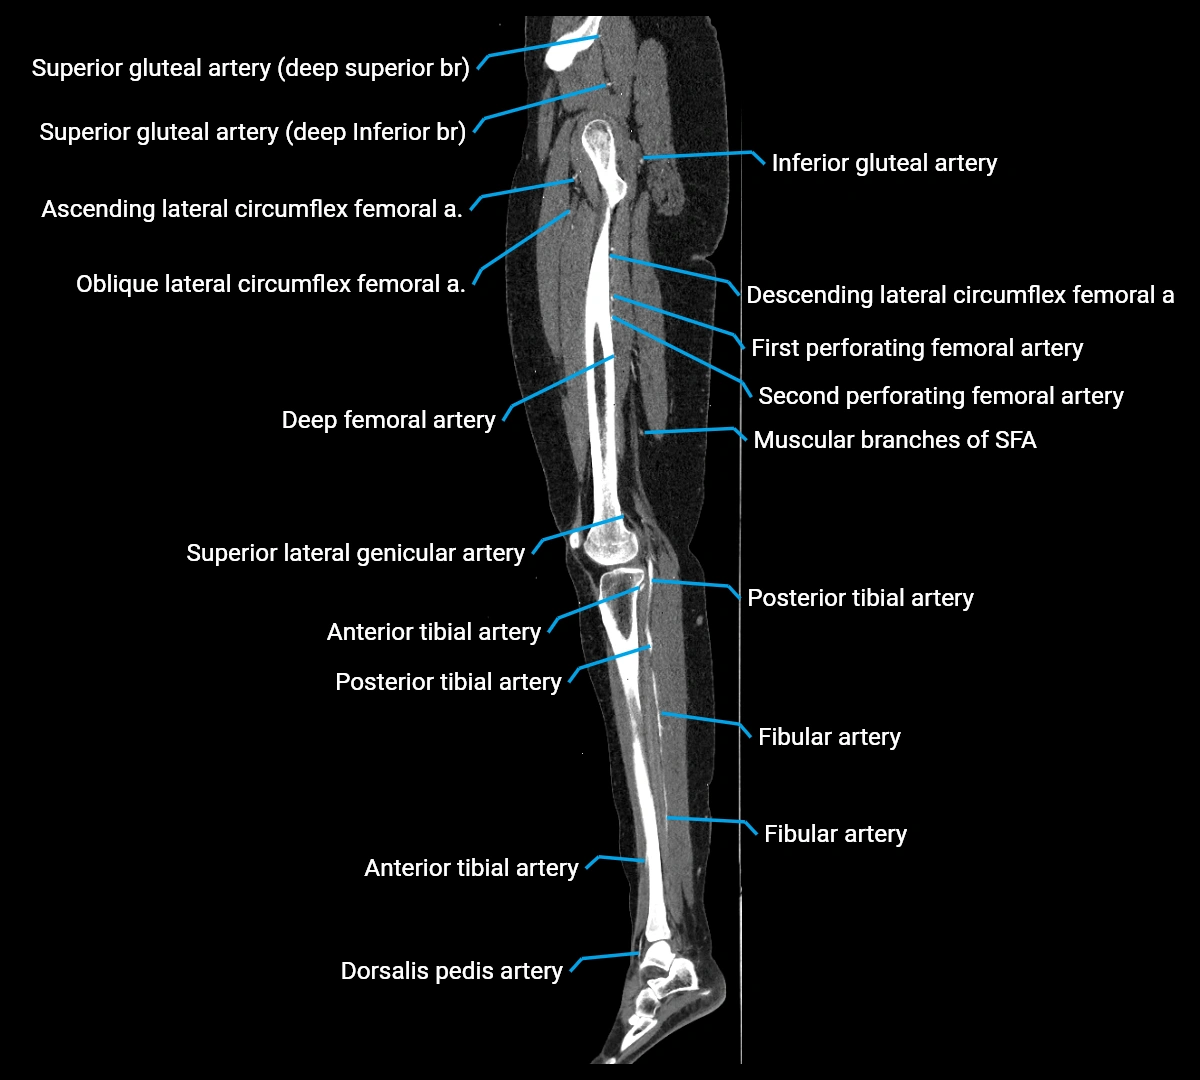

CT Appearance

Non-contrast CT:

• Appears as a tubular soft tissue structure anterior to vertebral bodies

• Calcified atherosclerotic plaques appear as hyperdense foci along the wall

• Useful for screening abdominal aortic aneurysm (AAA) size and mural calcification

Contrast-enhanced CT (CTA):

• Gold standard for abdominal aortic imaging

• Provides excellent detail of lumen, wall, aneurysm, thrombus, and branch vessels

• Multiplanar and 3D reconstructions help in aneurysm measurement, stent graft planning, and dissection evaluation

• Detects acute rupture, traumatic injury, or occlusion with high sensitivity

CT images

image